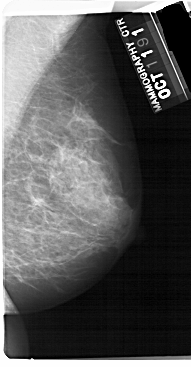

A_1432_1.LEFT_MLO

LEFT_MLO LINES 5491 PIXELS_PER_LINE 2731 BITS_PER_PIXEL 12 RESOLUTION 43.5 OVERLAY